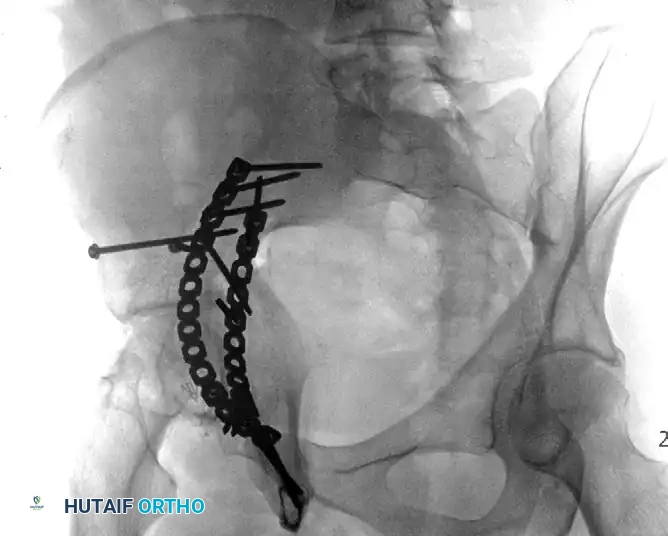

Both-Column Fractures and Indirect Reduction

Both-column fractures represent complete dissociation of the articular surface from the axial skeleton. These complex injuries often require extensive exposures or combined approaches. However, when treated through an ilioinguinal approach, indirect reduction techniques are frequently employed to restore the acetabular dome, with fixation placed on the internal surfaces of the pelvis to buttress the columns.

FIGURE 56-34: Both-column acetabular fracture treated through an ilioinguinal approach with indirect reduction of the acetabulum and fixation placed on the internal surfaces of the pelvis.